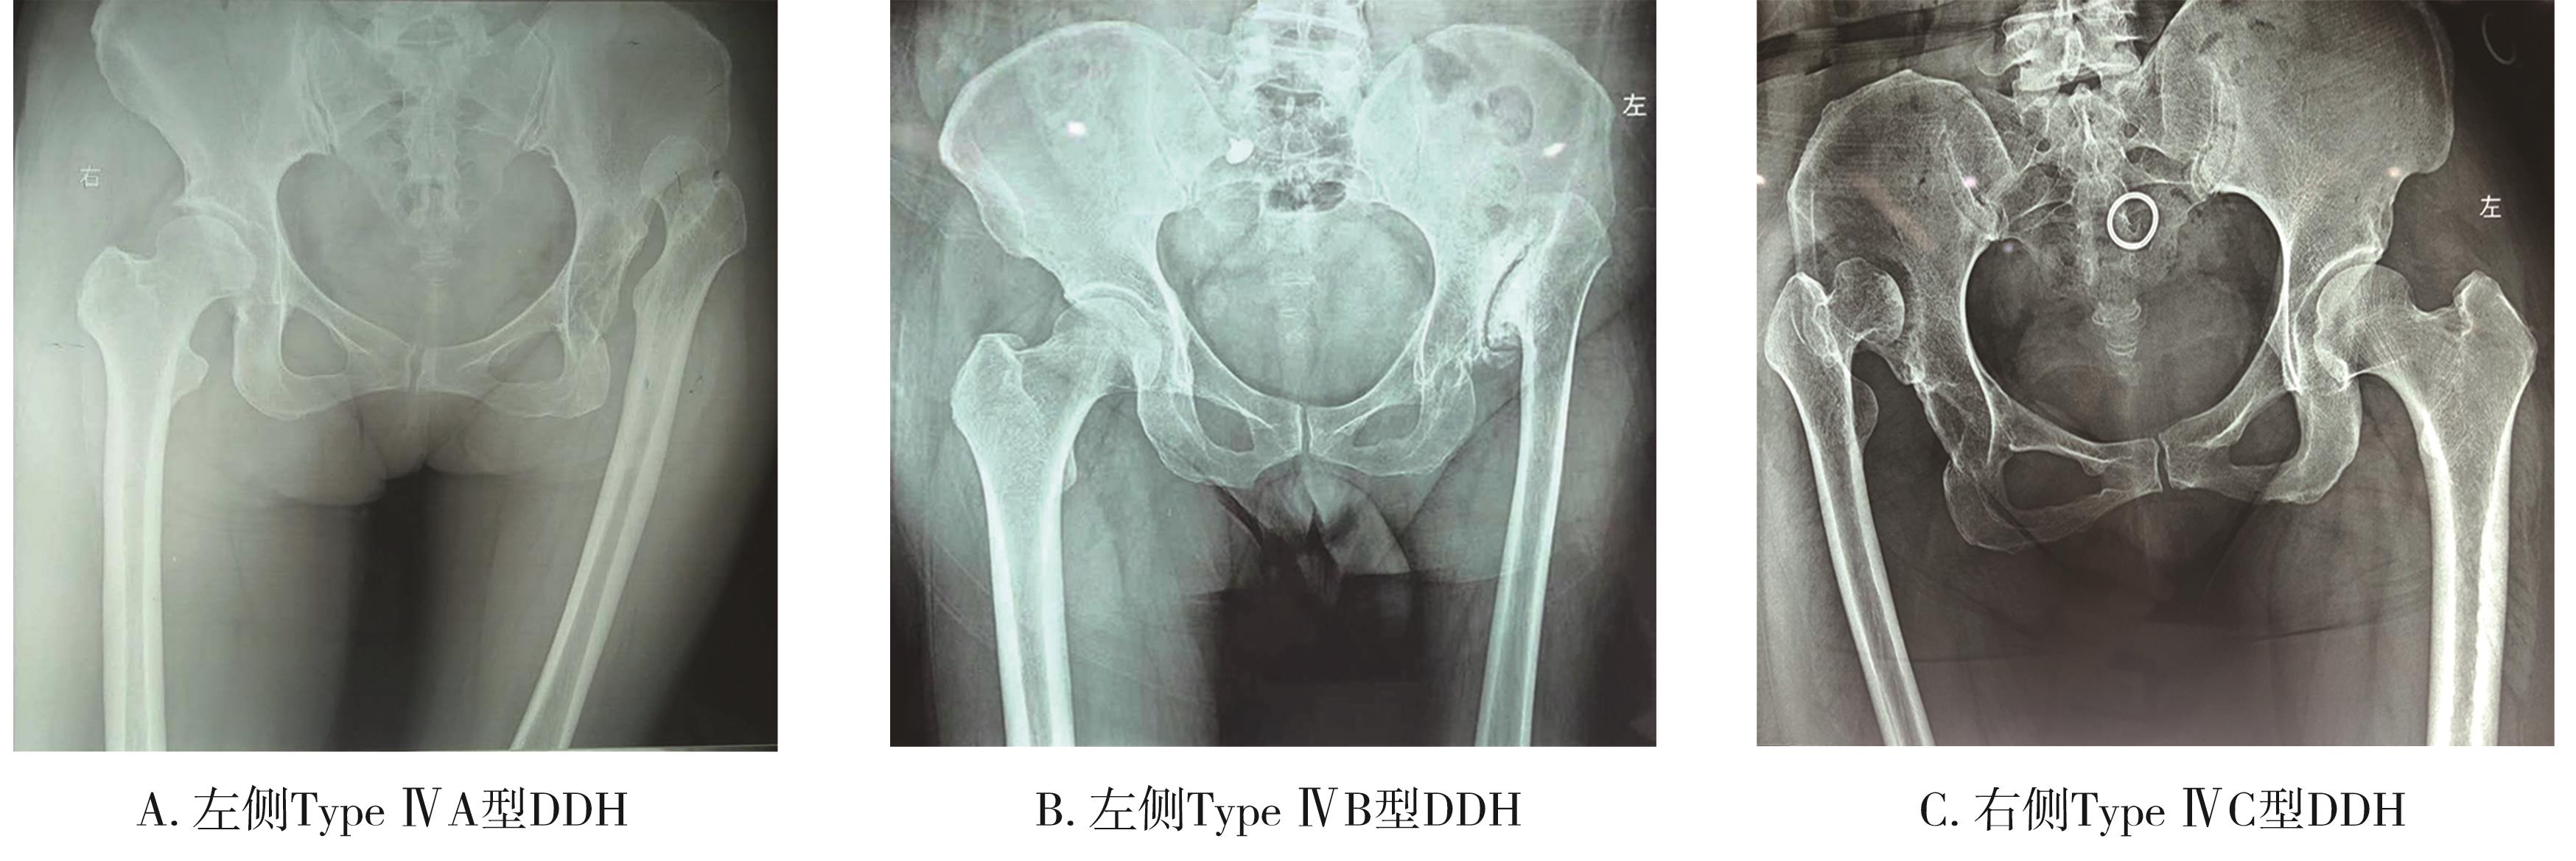

• 自体股骨头结构植骨重建髋臼辅助THA在改良CROWE Type ⅣB型DDH中的临床疗效分析

2024, 49(3):340-345. DOI: 10.13406/j.cnki.cyxb.

摘要 (37) HTML (42) PDF 4.06 M (60) 评论 (0) 收藏

摘要:目的 分析和总结自体股骨头结构植骨重建髋臼辅助全髋关节置换术(total hip arthroplasty,THA)治疗改良Crowe Type ⅣB型成人髋关节发育不良性脱位(developmental dysplasia of the hip,DDH)患者的临床疗效。方法 按照改良Crowe分型,选取山东大学齐鲁医院德州医院关节外科2015年8月至2023年3月收治的Type ⅣB型DDH患者26例,其中男25例,女1例,采用自体股骨头结构植骨重建髋臼辅助THA,记录患者手术时间、术中失血量、术中术后输血量、术后血红蛋白、手术相关并发症和骨愈合时间等,并行骨盆正位X线片了解假体位置、假体骨长入、假体松动以及骨愈合情况等,采用视觉模拟评分表(visual analogue scale,VAS)评价髋关节的疼痛不适,采用髋关节Harris评分和Western Ontario and McMaster Universities Osteoarthritis Index(WOMAC)来评价髋关节功能及临床疗效。结果 所有患者的平均随访时间(9.73±8.35)个月,术中出血平均为(715.38±143.37) mL,术中平均输血(415.38±282.41) mL,手术时间平均为(118.62±18.27) min,术后平均输血为(192.31±236.51) mL。所有患者转子下骨端、自体股骨头和假臼之间均骨愈合良好。髋关节VAS评分从术前6.73±0.45,至术后末次随访时VAS评分1.73±0.53,差异有统计学意义(P=0.000),髋关节活动度均较术前明显改善,髋关节Harris评分从术前24.27±1.66,至术后末次随访时Harris评分74.77±2.89,差异有统计学意义(P=0.000),WOMAC术前术后评分分别为130.08±5.72和67.85±3.23,差异均有统计学意义(P=0.000)。结论 自体股骨头结构植骨重建髋臼辅助THA治疗改良Crowe Type ⅣB型DDH,具有操作相对简单、固定牢固、手术相对安全和疗效确切的优点。